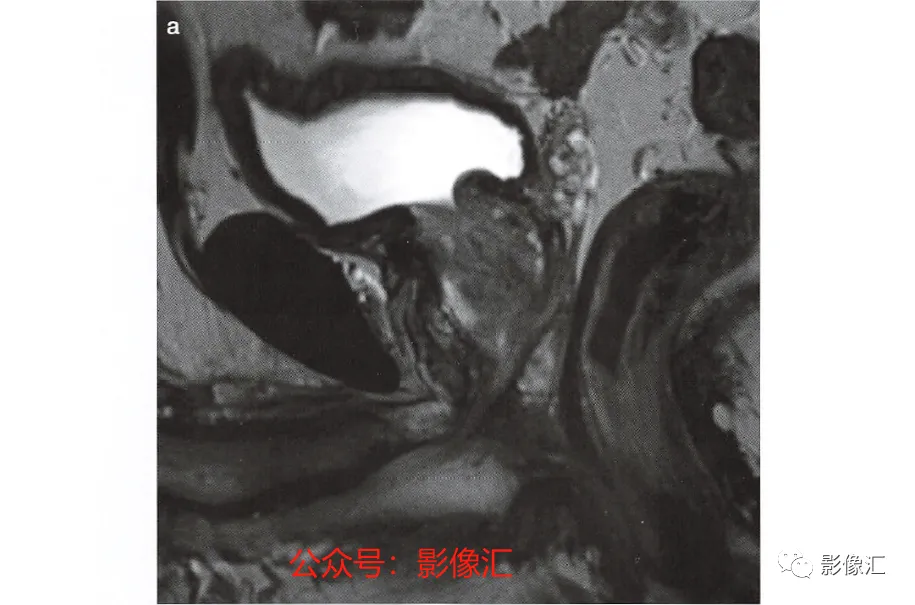

2. 正中矢状面(图2.20)